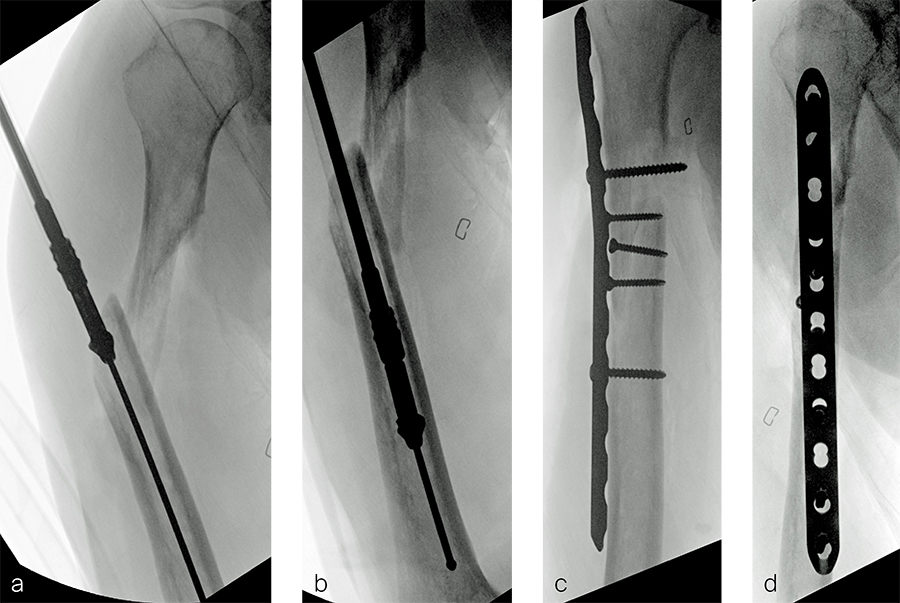

A 59-year-old man working for the city of Tulsa suffered an open distal tibia plafond fracture on the left leg when he fell into a sewer hole with raw sewage (Fig 1). The wound was grossly contaminated, and he was taken immediately to the operating room (OR) for incision and drainage and application of a spanning external fixator. Bone loss was noted anterior and medial (about 2.5 or 3 cm) but only about 2025% of the bone circumference.

After repeated incision and drainage, 2 days later the fracture was repaired with an anterior lateral tibial plafond plate (Fig 2). Vancomycin and tobramycin impregnated antibiotic beads were placed in the bone defect.

The patient was discharged on hospital day 6 to a rehabilitation facility with his left lower extremity in a splint and touch down weight bear allowance. He returned 2 weeks later with drainage from the medial traumatic wound. In addition, he had a gastrointestinal bleed from use of nonsteroidal antiinflammatory drugs. Once the gastrointestinal bleed was stabilized, he was taken the next day to the OR for another incision and drainage. Further, more significant, devitalized bone was resected, and an antibiotic cement spacer was placed (Fig 3). Deep culture samples were taken despite knowing the antibiotic resorbable beads had been placed in the wound at the time of initial closure. The plate was left in place, but a planned exchange plate/nailing was to be performed pending final culture results.

Cultures eventually yielded Klebsiella pneumoniae and Enterobacter cloacae. The patient was administered intravenous antibiotics for 6 weeks and was discharged home with therapy and nursing. He returned to the clinic with wound breakdown and an exposed cement spacer at 10 weeks after injury. Further bone debridement, spacer exchange, repeated culture samples, and plastic surgery were undertaken to help with wound coverage with a rotational flap. The microbiological culture was still positive for Klebsiella pneumoniae.

Two months later, the patient had a staged cement spacer removal and hardware removal followed by a new spacer placement (Fig 4). When microbiological cultures were negative for 5 days he was taken to the OR for definitive fixation and bone grafting. RIA bone graft from the ipsilateral femur was taken, a new anterior lateral plate was placed with an adjunct IM nail (and angle stable screws) as the distal plafond was now one articular block (Fig 5).